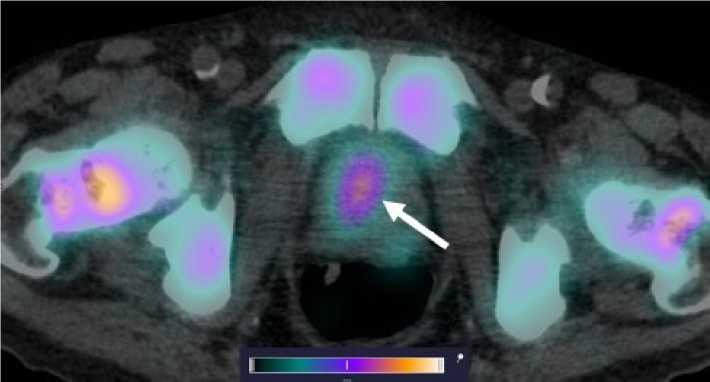

У 4 пациентов, вошедших в исследование, по данным референсных методов исследования, было выявлено метастатическое поражение костных структур, у 2 пациентов — поражение ЛУ. Накопление [99mTc]Tc-HYNIC-PSMA в патологических участках отмечалось у 3 больных с костными метастазами (SUVmax по всем костным очагам 28,57 ± 16,09) и у одного пациента с поражением ЛУ (SUVmax 15,32 ± 8,11). Примеры накопления [99mTc]Tc-HYNIC-PSMA в ПСМА-позитивных костных и лимфогенных метастазах представлены на рис. 4, 5.

Рис. 5. MIP-реконструкция, КТ и совмещенное ОФЭКТ/КТ изображение больного раком предстательной железы с множественными метастазами в кости и лимфатические узлы малого таза через 2 ч после инъекции [99mTc]Tc-HYNIC-PSMA. На ОФЭКТ-КТ изображении стрелкой отмечено накопление РФЛП в паховом лимфатическом узле слева (1) SUVmax 22; бедренной кости слева (2) SUVmax 53; лонной кости слева (3) SUVmax 22,8

Fig. 5. MIP reconstruction, CT and SPECT/CT image of a patient with prostate cancer with multiple metastases to bones and pelvic lymph nodes 2 hours after injection of [99mTc]Tc-HYNIC-PSMA. Аccumulation of radiopharmaceutical in the pathological areas is indicated by the arrow on the SPECT-CT image: inguinal lymph node on the left (1) SUVmax 22; femur on the left (2) SUVmax 53; pubic bone on the left (3) SUVmax 22.8